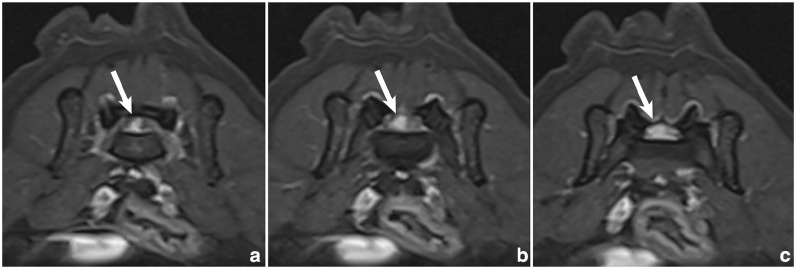

Case summary: A 10-year-old female spayed domestic shorthair cat was evaluated for a 6-week history of abnormal tail carriage and constipation. Examination revealed tail paresis and pain over the lumbosacral and sacrocaudal articulations and on tail manipulation. MRI revealed a contrast-enhancing mass within the vertebral canal over the lumbosacral disc space, compressing the cauda equina. The mass filled the epidural space, resulting in complete attenuation of the cerebrospinal fluid signal. Laminectomy and durotomy were performed over L7-S1, revealing white, firm material within the subarachnoid space. Microscopically, the material was consistent with degenerative intervertebral disc material. Postoperatively, the clinical signs resolved completely.

Relevance and novel information: Intervertebral disc herniation (IVDH) is uncommon in cats, with most cases involving extradural compression of nervous tissue. Reports describing intramedullary intervertebral disc extrusions in cats are rare. To the authors' knowledge, the present case is the first reported intradural-extramedullary intervertebral disc extrusion in a cat. Although MRI can often delineate extradural lesions, it can be insensitive in differentiating intradural-extramedullary from intramedullary lesions. In the present case, the location of the lesion within the vertebral canal at the lumbosacral disc space made the determination of the lesion's location with respect to the meninges challenging. Moreover, the strong contrast enhancement of the lesion raised an index of suspicion for neoplasia. Surgical intervention and histopathology confirmed an intradural-extramedullary IVDH. The present case adds to a growing body of literature regarding IVDH in cats and details the imaging findings of intradural-extramedullary IVDH in a cat.